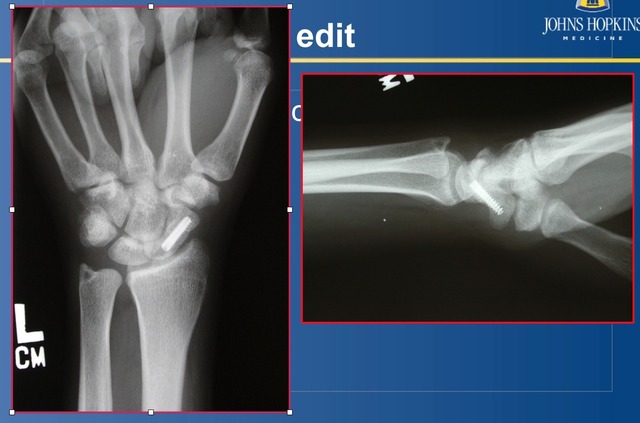

若采用螺钉固定,则需要将螺钉中心放置(图 4)。

图 4